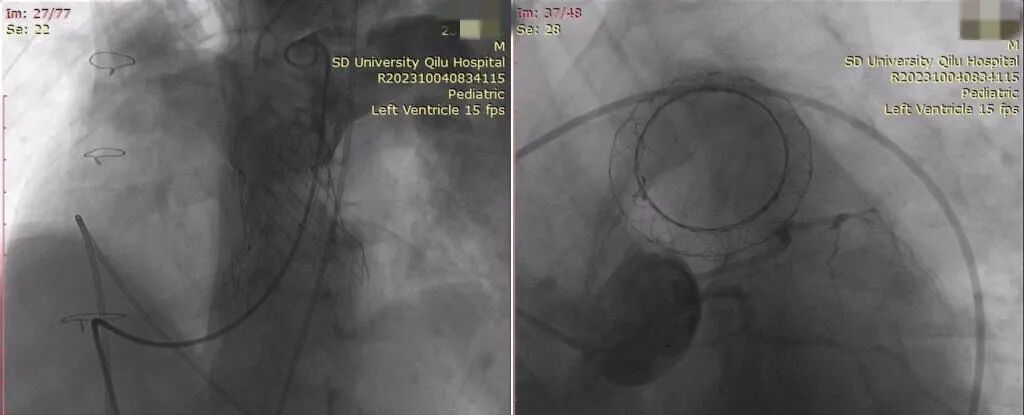

左图:VenusP-Valve瓣膜释放完成,造影显示位置准确,形态良好,无明显瓣膜反流及瓣周漏;

右图:重复行冠脉造影显示冠脉血流通畅